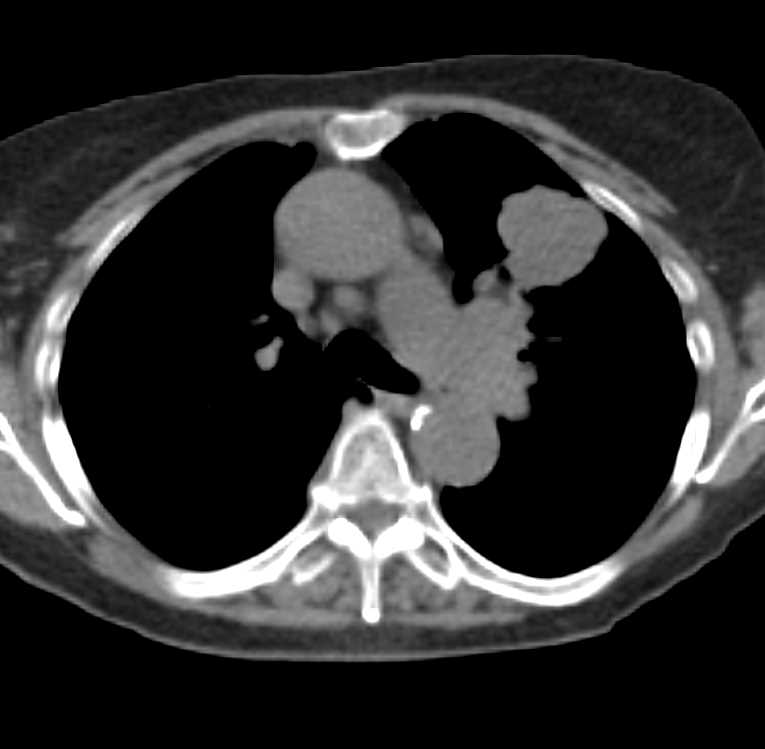

Lung Cancer with Left Hilar Adenopathy